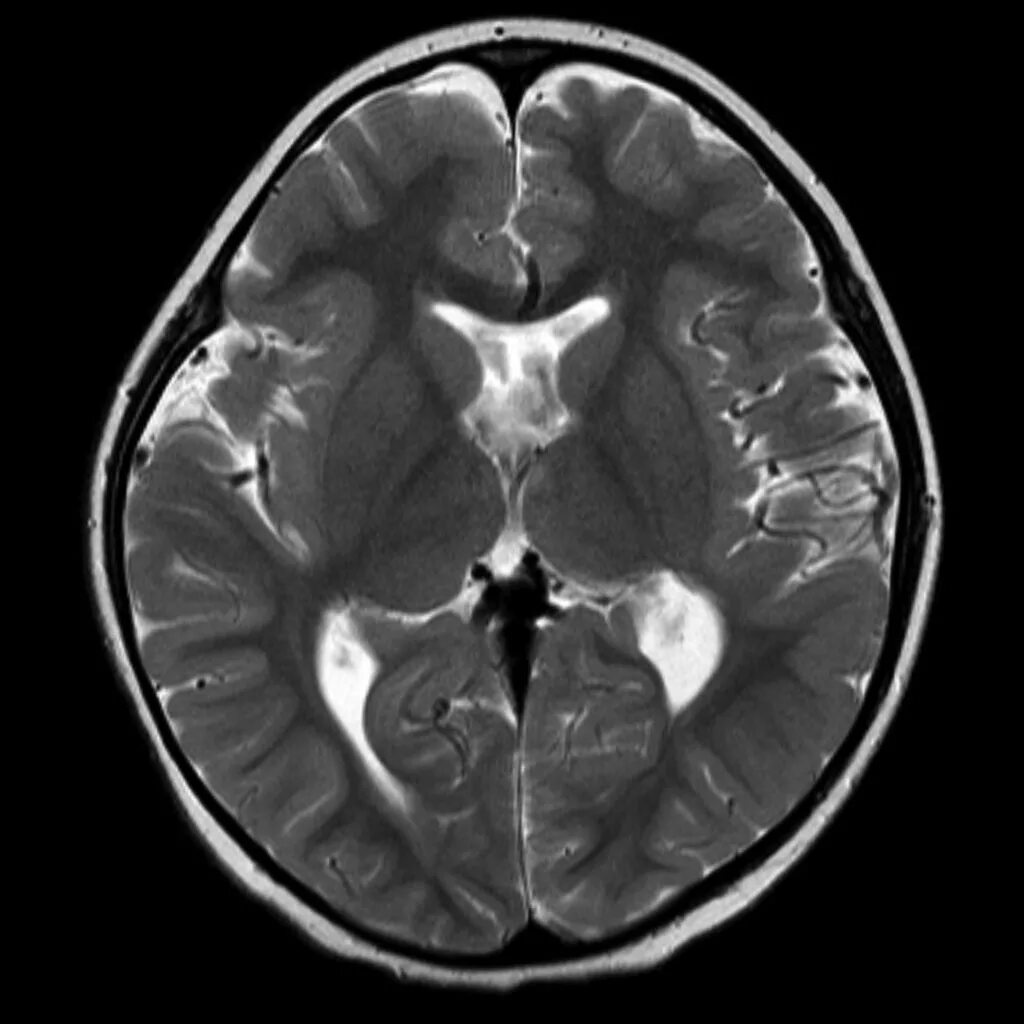

Незаращение листков прозрачной перегородки